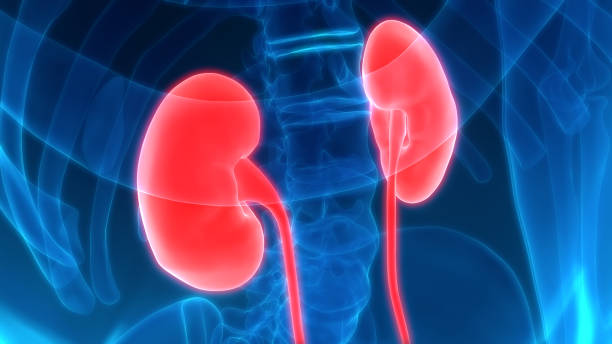

신장은 우리 몸에서 침묵의 장기 중 하나로 알려져 있습니다.

이는 신장의 병이 발생하더라도 증상이 미미하게 나타나기 때문입니다.

신장은 양쪽 옆구리에 위치하기 때문에 신장에 문제가 생기면 허리 통증이 발생할 수 있습니다. 허리가 아플 때에는 신장 검사를 고려해야 합니다.